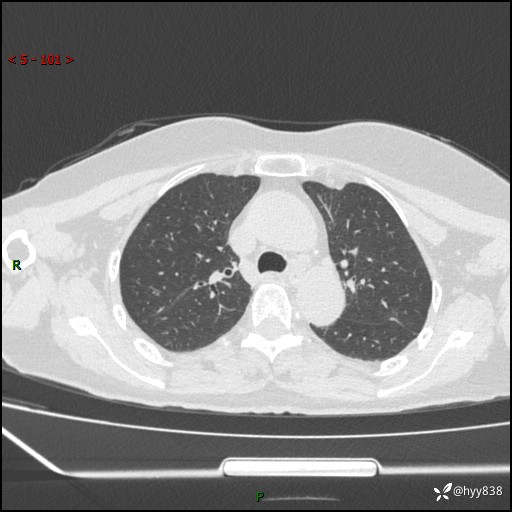

老年女性,偶然发现肺结节10天。结节不大,空洞不小,还牵拉胸膜---结果公布~

主诉:体检发现肺结节10余天

现病史:患者10余天前因“左侧鼻塞伴鼻腔异味2月”就诊于我院耳鼻喉科,查胸部CT示:左上肺结节影,建议复查。患者偶有咳嗽、咳痰,多咳白痰,无畏寒、发热,无胸痛、呼吸困难等,现为进一步明确肺结节性质,就诊于我科门诊。现以“孤立性肺结节”收住我科。 起病来,患者精神、食欲、睡眠尚可,体力、体重无明显变化。

胸部CT(2024.7.16)